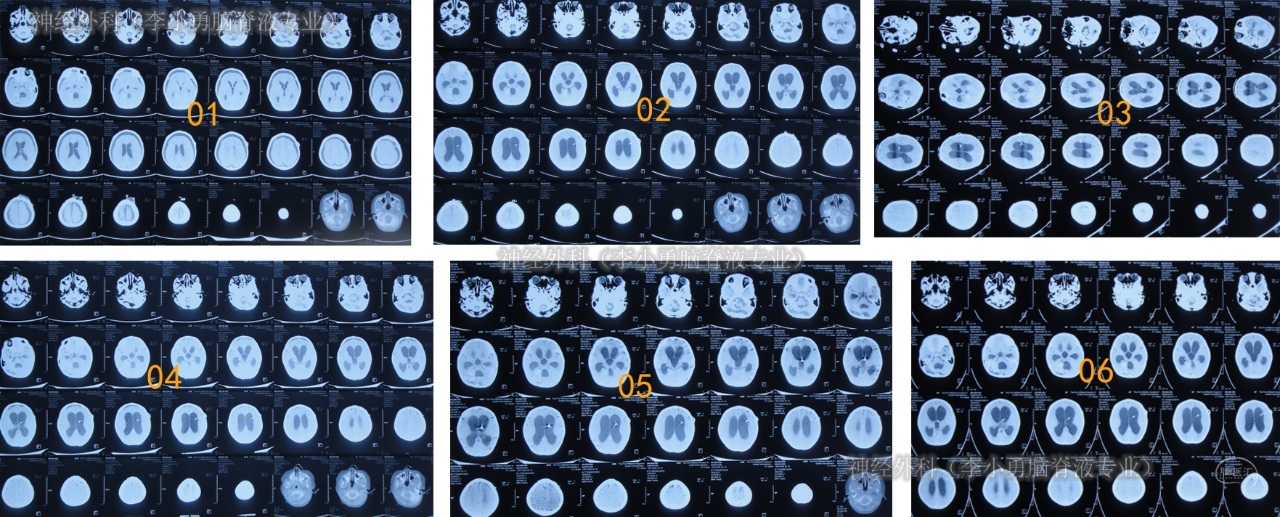

术后症状有短暂好转后但又出现了双眼凝视,精神状态差,术后5天的时间内2次查头颅CT示脑室再次明显扩大(图-1),持续Ommaya囊外接引流瓶引流脑脊液。

图-1:2次查头颅CT该院继续治疗40天,期间6次查头颅CT(图-2)均示脑室扩张不断地加重。

图-2:6次查头颅CT

术后半月余期间3次查头颅CT(图-3)均示脑室仍扩张。

图-3:3次查头颅CT